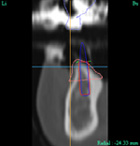

CT撮影

CT装置で撮影し、あごの骨の状態を診断します。

CTにて撮影したデータを、3次元画像解析システムにより、患者さんの神経や骨の状態を細部まで分析します。